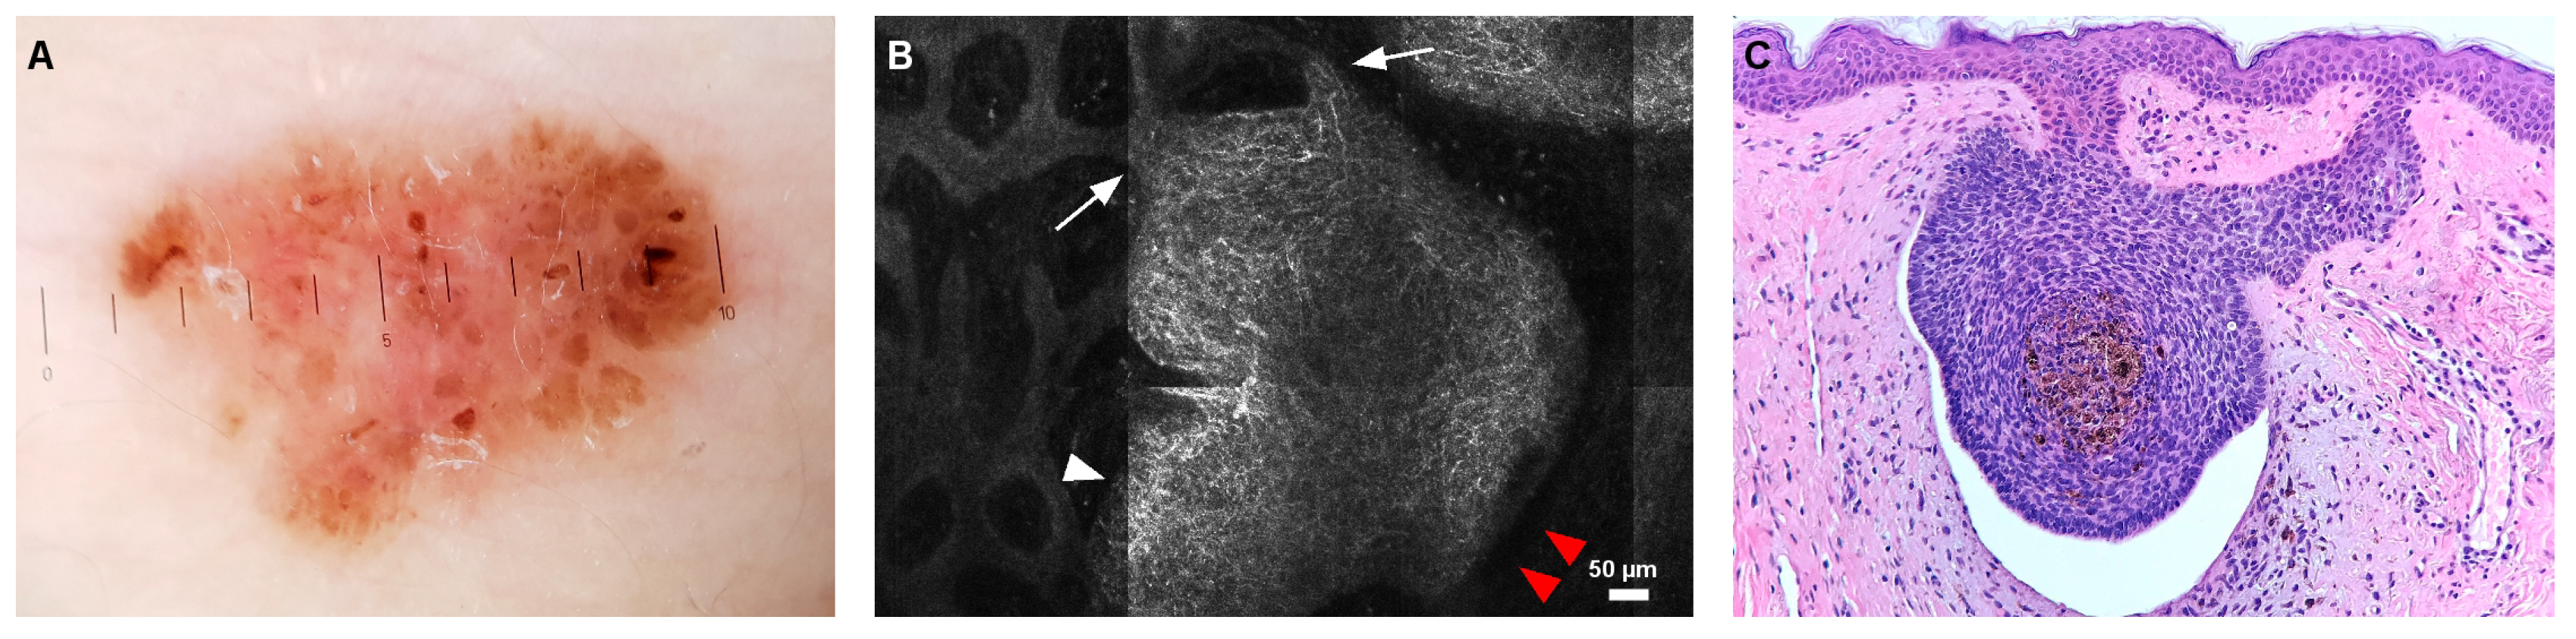

- Ghita, M.A.; Caruntu, C.; Rosca, A.E.; Kaleshi, H.; Caruntu, A.; Moraru, L.; Docea, A.O.; Zurac, S.; Boda, D.; Neagu, M. Reflectance confocal microscopy and dermoscopy for in vivo, non-invasive skin imaging of superficial basal cell carcinoma. Oncol. Lett. 2016, 11, 3019–3024. [Google Scholar] [CrossRef] [PubMed]

- Caruntu, C.; Boda, D.; Gutu, D.E.; Caruntu, A. In vivo reflectance confocal microscopy of basal cell carcinoma with cystic degeneration. Rom. J. Morphol. Embryol. 2014, 55, 1437–1441. [Google Scholar]

- Casari, A.; Pellacani, G.; Seidenari, S.; Cesinaro, A.M.; Beretti, F.; Pepe, P.; Longo, C. Pigmented nodular basal cell carcinomas in differential diagnosis with nodular melanomas: Confocal microscopy as a reliable tool for in vivo histologic diagnosis. J. Skin Cancer 2011, 2011, 406859. [Google Scholar] [CrossRef]

- Peppelman, M.; Wolberink, E.A.W.; Blokx, W.A.M.; van de Kerkhof, P.C.M.; van Erp, P.E.J.; Gerritsen, M.-J.P. In vivo diagnosis of basal cell carcinoma subtype by reflectance confocal microscopy. Dermatology 2013, 227, 255–262. [Google Scholar] [CrossRef]